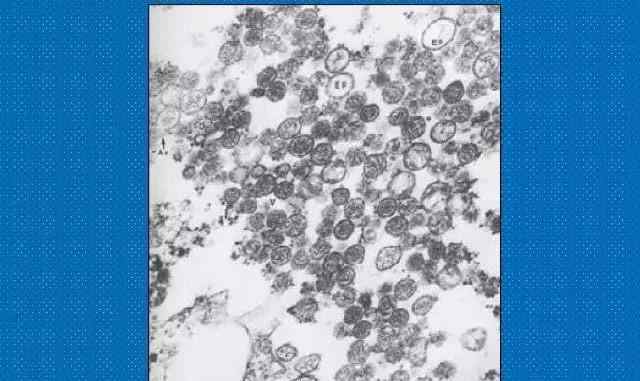

汉坦病毒的病原体

汉坦病毒的透射电镜照片汉坦病毒的透射电镜照片